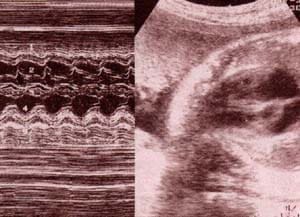

| fig 35. a nivel ventricular. 37 semanas. pared ventrículo derecho (1). válvula tricúspide (2). septum i-v (3). válvula mitral (4). pared ventrículo izquierdo (5). | fig 36. a nivel auricular. 32 semanas. pared aurícula derecha (1). válvula tricúspide (2). septum i-a (3). válvula mitral (4).pared aurícula izquierda (5). |

fig 37. a nivel del foramen oval. 36 semanas.

pared aurícula derecha (1). septum i-a (2).

válvula del foramen oval (3). pared aurícula izquierda (4).